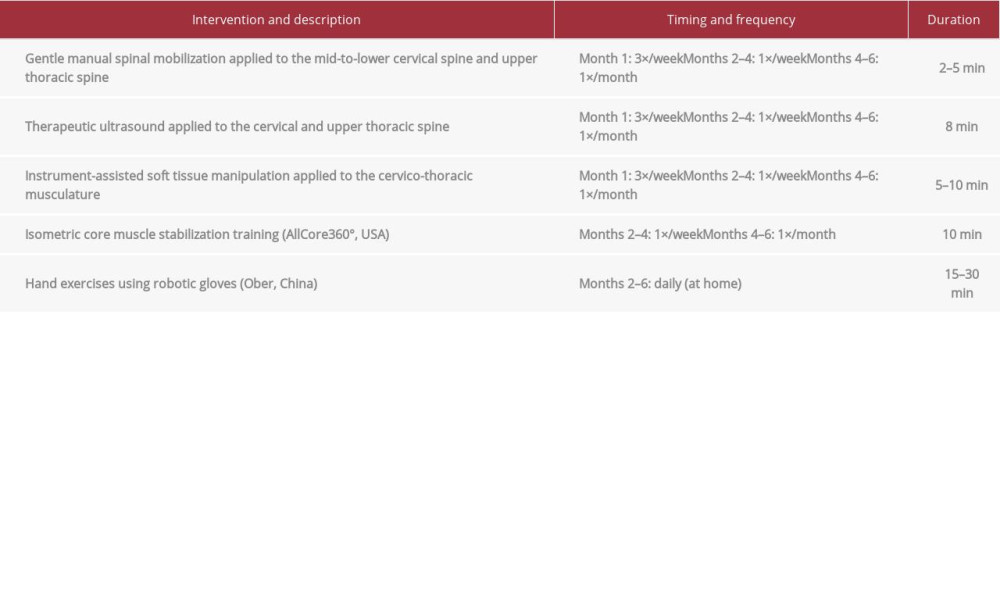

The patient consented to a chiropractic treatment plan which began at a frequency of 3 visits per week and included a variety of therapies (Table 1). Gentle manual spinal mobilization was administered to the mid to lower cervical and upper thoracic segments to alleviate muscle hypertonicity and restore spinal mobility (Figure 5). This treatment was well tolerated by the patient. Therapeutic ultrasound and instrument-assisted soft tissue manipulation (also called gua sha) using a massage tool (Strig, Korea) was applied to further alleviate muscular hypertonicity and reduce pain (Figure 6).

After the first month of treatment, the patient’s reported neck pain severity decreased to 4 out of 10. Given the patient’s improvement, her visit frequency was reduced to once per week. After the second month of treatment, all numbness symptoms were resolved. The patient had stopped taking tramadol and was now able to use chopsticks. Low-impact isometric core muscle stabilization training was added, with the goal of strengthening the paraspinal muscles and spine and improving posture. This was accomplished by having the patient sit in a robotic device that rotated slowly at different angles of inclination while the patient maintained a neutral spine position; this was performed for 10 min per visit (AllCore360° [29], USA; Figure 7)

Hand exercises were also added, which were conducted using robotic gloves (Ober, China). These were rented to the patient for home use for 15 to 30 min per day (Figure 8). This type of robotic glove is used to augment hand motion for patients with weakness or functional deficits of the hand and fingers and has been previously studied for use with patients with spinal cord injury [30]. In the setting used, the device matched the patient’s own finger movement and provided mechanical assistance. The degree of assistance was reduced as the patient regained strength. The patient was recommended to perform tasks such as opening and closing the hands and squeezing a ball with the aid of the gloves.